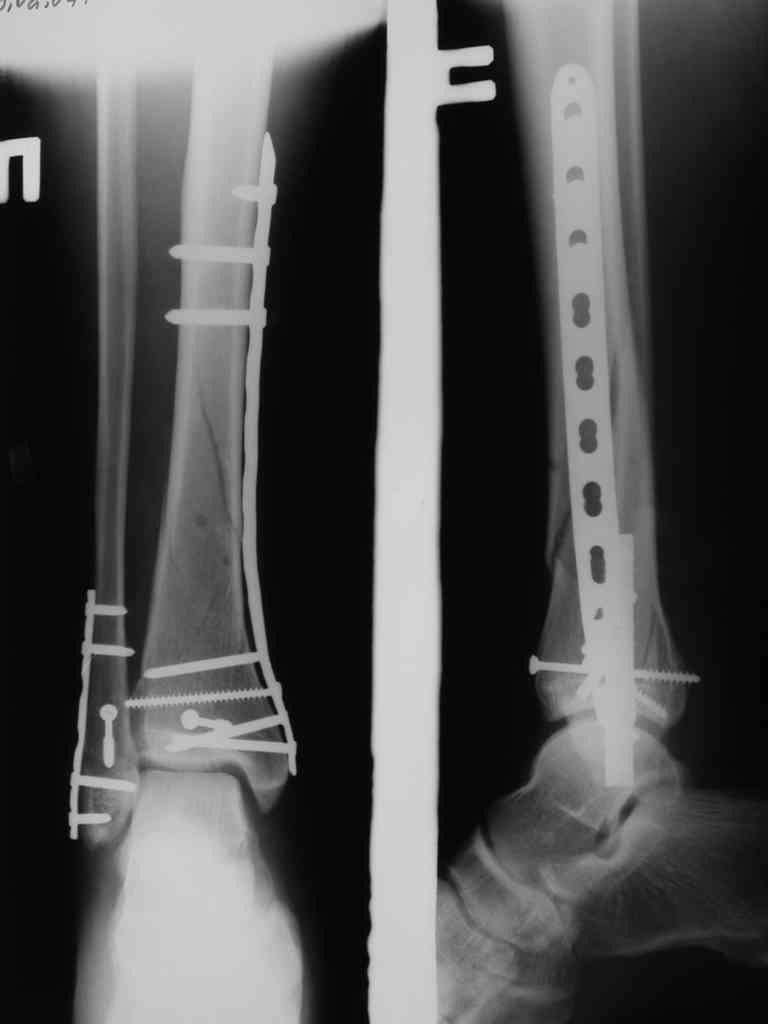

Сегодня прооперировали. Длительность 4-50. Начали как и говорил сверху вниз линейным разрезом - фиксация задне-латерального отломка к проксимальному 2мя винтами, затем "прилепили" к ним передне-медиальный (пришлось повозиться - была интерпозиция и довольно "сложный" винт) - к проксимальному 1 винтом и к задне-латеральному 1 винтом.Кстати на фото видно - у передне-медиального отломка еще осколок в области сустава, несколько смят. Далее началось веселье - второй доступ - задне-наружный к латеральной лодыжке и заднему краю, но оказалось, что задний край больше задне-медиальный (по снимкам было непонятно). Плюс к этому репозиция его мягко говоря сложновата (больной на спине, стол низкий и не поднимается). В общем выставили, фискировали 2мя винтами, на ЭОПе вроде стал, только верх отошел. Латеральную лодыжку заведующий решил интрамедуллярно (не хотел еще винты толкать), сначала 3мм спицей - нестабильно, затем 4мм стержень (не помню по автору) - ОК (кстати в месте перелома мелкая крошка - дефект до 5х7 мм по кортикалу). Ну медиальная лодыжка стандартно - третий разрез - винт 3,5 мм. Визуально все стабильно. На Р-контроле - видна небольшая ступенька заднего края по одному из контуров.

Рентгенограммы

На фото простой суставной, метафиз. оскольчатый с переходом на диафиз перелом, пластина MIPO.